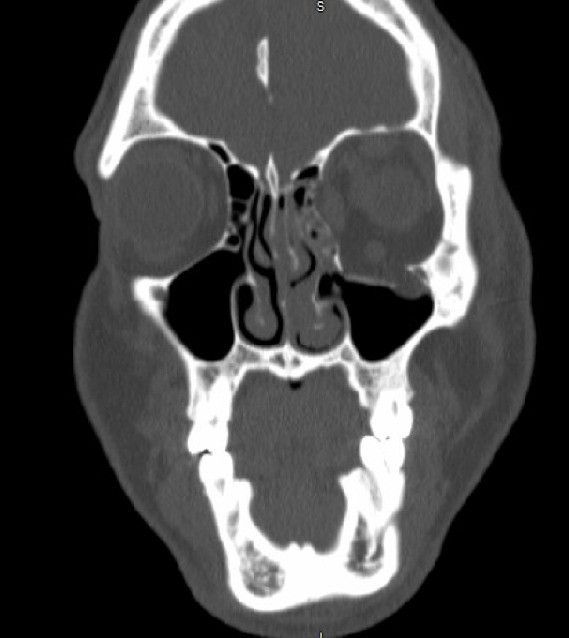

Томограмма глазных орбит, демонстрирующая перелом дна левой глазницы с грыжей в левую верхнечелюстную пазуху.